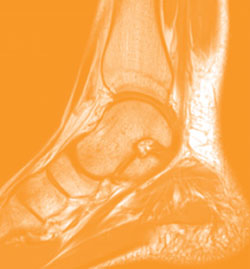

Computed tomography (CT) scanners X-ray the body from a number of angles and combine the data to get a comprehensive, 3D picture. In some cases the patient is given a "contrast agent" by mouth or injection to make the image crisper. These contrast agents— solutions of barium or iodide, for example—each light up a particular body organ or system.

Image courtesy of Radiological Society of North America